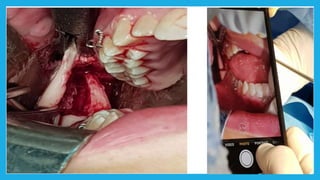

Mandibular orthognathic surgery Itcan be divided into several section:-  Surgery in which the jaw is moved in antrio-posterior direction by an osteotomy either in the ramus or body of the mandible  Surgery to the dentoalveolar area, such as segmental surgery to shift the teeth and alveolus but maintaining the integrity of the lower part of the mandible  Surgery into the chin, moving it in superior , inferior , posterior or anterior direction sometimes accompanied by reshaping

Ramus procedures  Bilateralsagittal split osteotomy(BSSO)

 Vertical subsigmoidosteotomy (VSS)